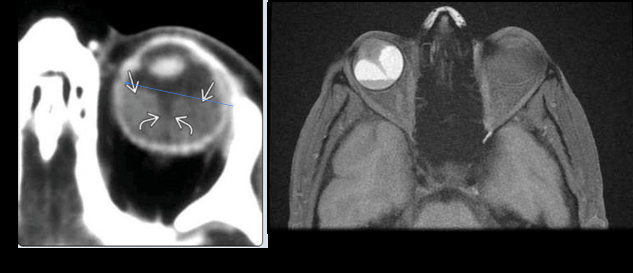

12

Q

Imagen en retinoblastoma

A

Calcificaciones intraoculares

TC- ver calcificaciones

RM - mapeo tumor

USG - lesión hiperecogénica con calcificaciones

13

RM en retinoblastoma

Evaluar implicaciones intra y extraoculares / intracraneales

Hemorragia retinal